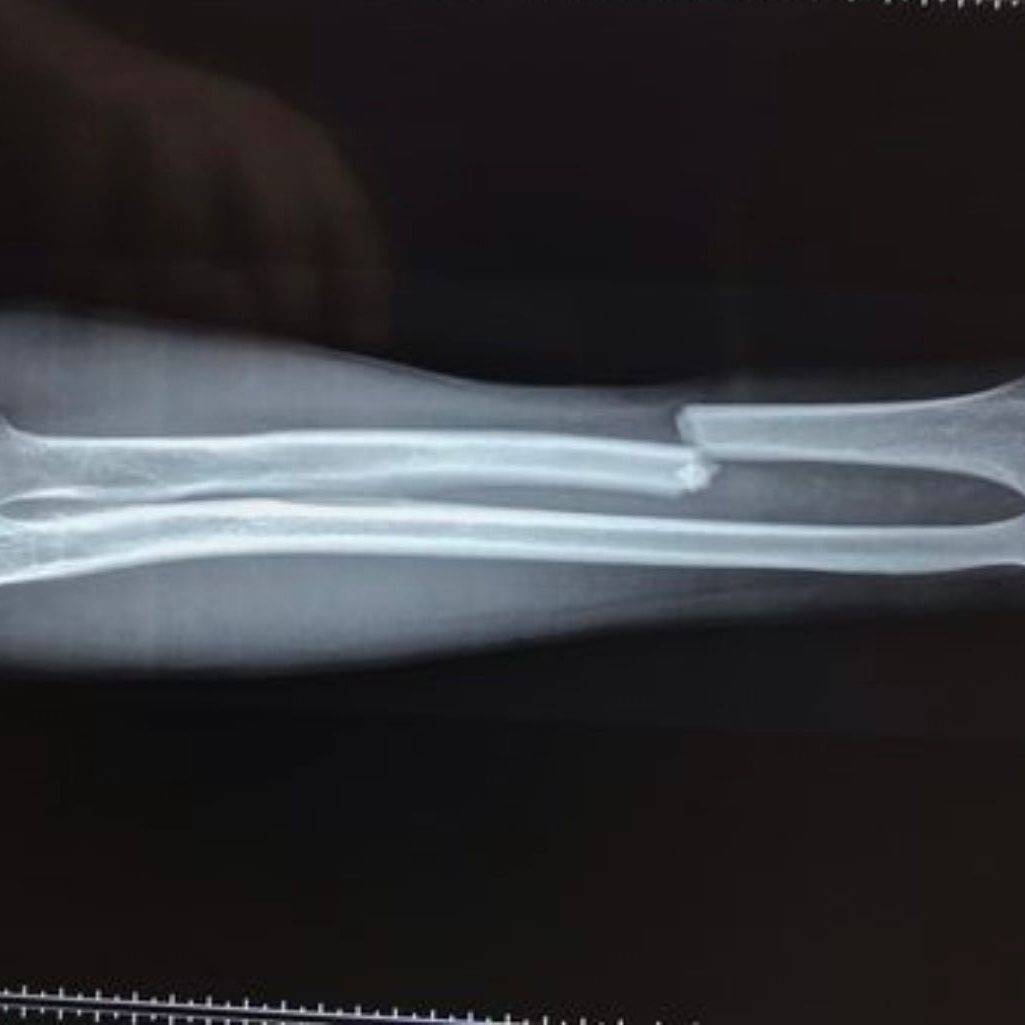

Adult and Paediatric Orthopaedic Trauma

Injuries can happen to anyone, at any age. Our practice is skilled in treating both adult and paediatric orthopaedic trauma. From fractures and dislocations to more complex injuries, the goal is to provide prompt and effective treatment to aid quick and full recovery. Utilising the latest techniques and technologies, we manage trauma cases to ensure the best possible outcomes.